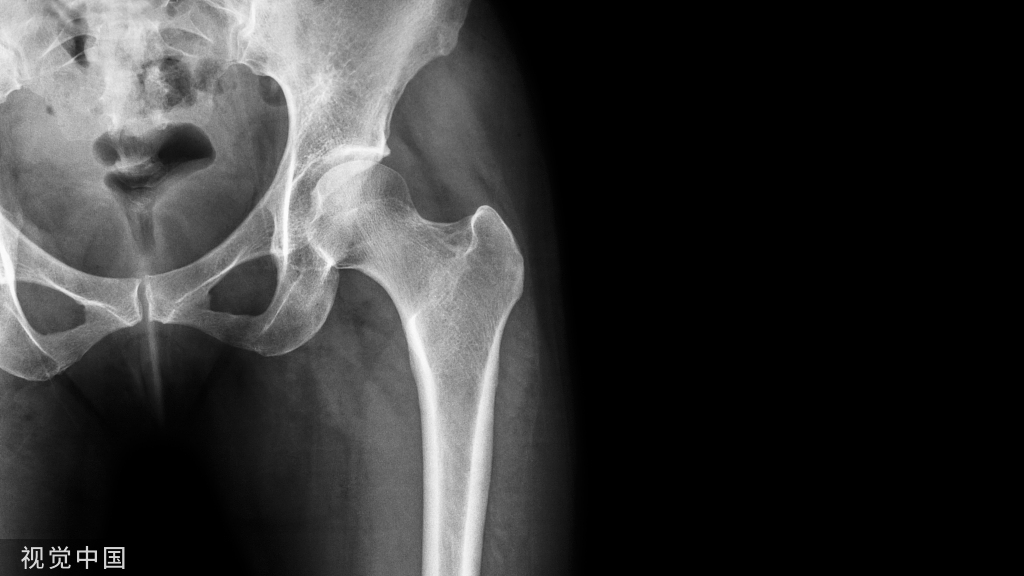

骨折手法复位的三项基本原则!

骨折的复位非常重要,不论是保守治疗还是手术治疗都需要复位。早期的复位可以明显减轻患者疼痛,减少手术困难,缩短手术时间。部分骨折如果复位后稳定可选择保守治疗。